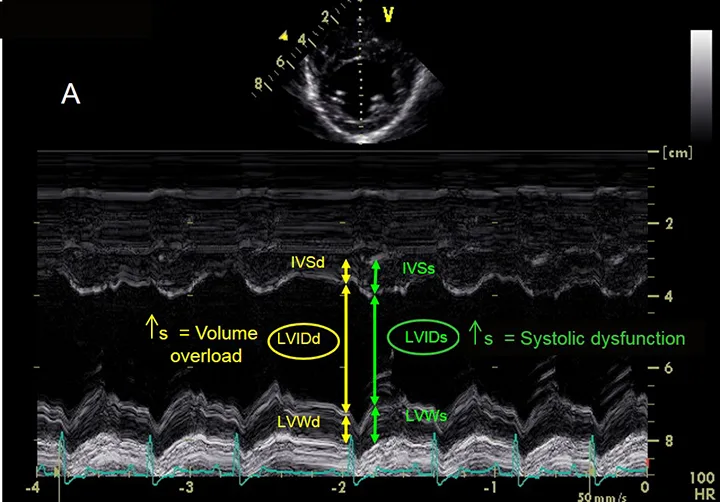

Labeled M-mode echocardiogram demonstrating measurements of features of the left ventricle.

FIGURE 3A

Left ventricular measurements using M-mode echocardiography. During both systole and diastole, this image demonstrates interventricular septum thickness (IVSs, IVSd), left ventricular (LV) internal dimension (LVIDs, LVIDd), and LV free wall thickness (LVWs, LVWd). Increased LVIDd causes left ventricular volume overload, whereas increased LVIDs results in systolic dysfunction.